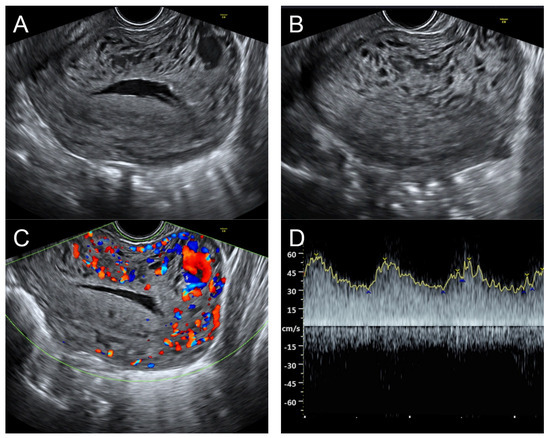

(A) Transabdominal grayscale ultrasound: transverse scans of suprapubic area showed suboptimal-quality image of the uterus, which displayed ill-defined soft tissue mass, non-visualized endometrial lining, hypoechoic areas of the uterus. No normal architecture of the uterus could be demonstrated. (B) Color flow mapping (the same area of figure (A)) showed markedly vascularized uterus, involving throughout the uterus intense vascularity with a chaotic, multidirectional flow. (C) Transvaginal color Doppler ultrasound showed markedly vascularized uterus, involving throughout the uterus intense vascularity with a chaotic, multidirectional flow. (D) Abdominal CTA revealed innumerable tortuous dilated vessels in the pelvic cavity, along the entire uterine wall. The lesions were fed by multiple arterial feeders, which were displayed as tortuous dilated arteries of the bilateral uterine arteries, right ovarian artery, and right inferior epigastric artery. Multiple draining veins demonstrated early venous opacification, namely the bilateral internal iliac veins and right ovarian vein. The CTA findings confirmed uterine AVM.

Management: Initial therapy included fluid resuscitation, blood transfusion, and tranexamic acid administration. Transcatheter uterine embolization of the bilateral uterine arteries, right ovarian artery, and right inferior epigastric artery was successfully performed, without immediate post-operative complications. The follow-up abdominal CTA at 8 weeks after the procedure showed no residual AVM, and the patient was healthy with no further abnormal bleeding at 2.5-year follow-up.